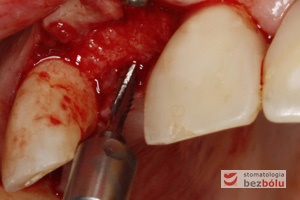

Proces implantacji – pierwsze wiertło pilotowe Lindemana pozwala ocenić gęstość kości i wyznaczyć pozycję implantu

Ustalenie pozycji implantu – wiertło Lindemana wyznacza nachylenie i oś długą dla wprowadzanego implantu